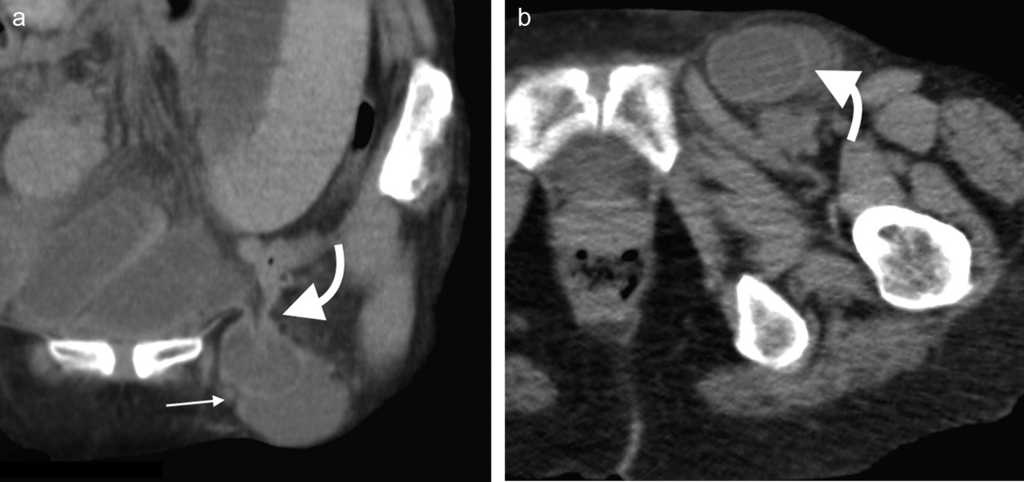

Menos frecuente que la inguinal, esta se produce cuando el contenido peritoneal penetra el canal femoral junto con la arteria y la vena femoral4. Esta región tiene una configuración más sencilla que el canal inguinal, se forma con el ligamento inguinal hacia arriba, el borde medial del m??sculo aductor hacia dentro, el m??sculo sartorio hacia afuera y los m??sculos psoas il??aco, pect??neo y el aductor largo haciendo de piso8. La principal característica del triángulo es la vaina femoral, que es una condensaci??n de la fascia profunda (fascia lata) del muslo y contiene, en direcci??n lateral-medial, a la arteria, la vena y el canal femoral1. Es más frecuente en mujeres y del lado derecho4.

En la TCMD el cuello del saco herniario se identifica como una estrecha protrusi??n a trav??s del anillo femoral, en direcci??n caudal al origen de los vasos epig??stricos inferiores y de forma medial a la vena femoral com??n, que frecuentemente aparece comprimida por el saco herniario (fig. 3). A veces en la evaluaci??n cl??nica resulta dif??cil distinguir una hernia femoral de una inguinal, por lo que la TCMD tiene un rol importante en su diferenciaci??n y valoraci??n del contenido2. Lo m??s com??n es visualizar asas de intestino delgado dentro del saco herniario, pero tambi??n se puede encontrar el ap??ndice dentro de este canal. Esto ??ltimo es poco frecuente (1% de los casos) y recibe el nombre de hernia De Garengeot9 (tabla 2).

Su diagn??stico cl??nico no es f??cil porque esta hernia se extiende entre las capas musculares o fasciales de la pared abdominal anterior. El orificio herniario puede ser peque??o, dif??cil de localizar y tener grasa omental (fig. 5a), asas de intestino delgado (fig. 5b) o implantes metast??sicos12 (fig. 6).